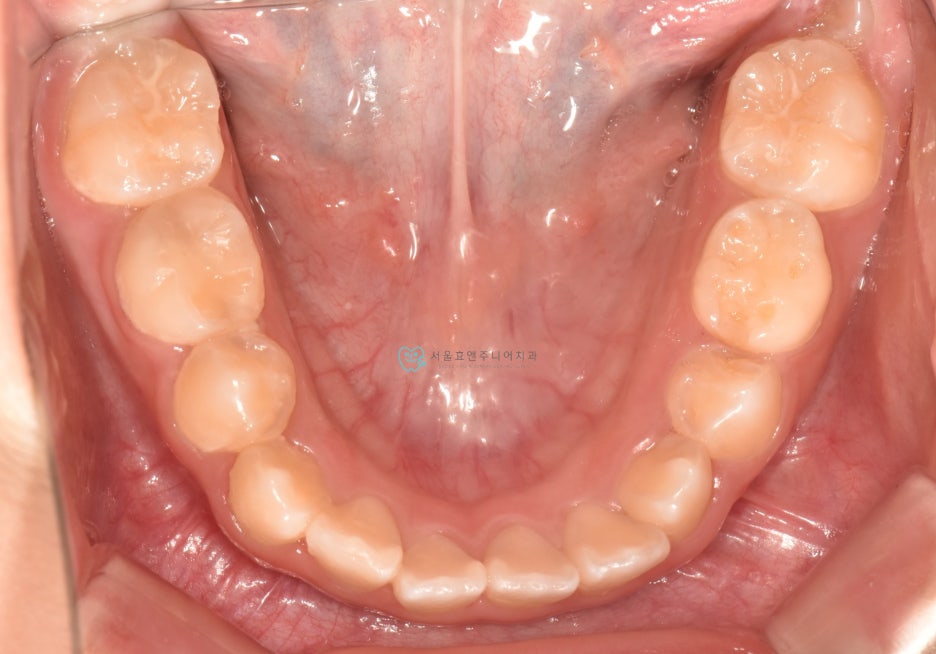

초진사진입니다

초진사진입니다. 11세 5개월 환아로, 반대교합을 보이고 있습니다. 반대교합으로 인해 치아가 부딪혀 치은퇴축(잇몸이 내려감)도 보이고 있네요.(화살표)